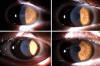

Paciente miope leve, sin antecedentes personales de interés, que tras una semana operado de LASIK (microqueratomo manual Moria LSK One y láser excímer Technolas 217 Z de Bausch & Lomb) sin incidencias, acude a la consulta con una opacidad corneal central, adelgazamiento y estrías en la misma zona, acompañado de hipermetropización y disminución de la agudeza visual. La imagen biomicroscópica era sugerente de necrosis estromal. Presentaba una DLK leve asociada. Cuadro parecido en ambos ojos, aunque mas intenso en el ojo derecho

El paciente fue tratado con corticoides tópicos durante una semana, debido a una queratitis lamelar difusa acompañante. Una vez resuelta la DLK se suspendieron paulatinamente los corticoides. La QCT se resolvió por completo en cuatro semanas más, sin necesidad de lavar quirúrgicamente la interfase (fig. 1).

Fig. 1: En la ilustración se ve la CTK en OD en cuadrante superior izquierdo y CTK en OI en cuadrante superior derecho. En el cuadrante inferior izquierdo se ve la resolución en OD y en el cuadrante inferior derecho la resolución del OI.